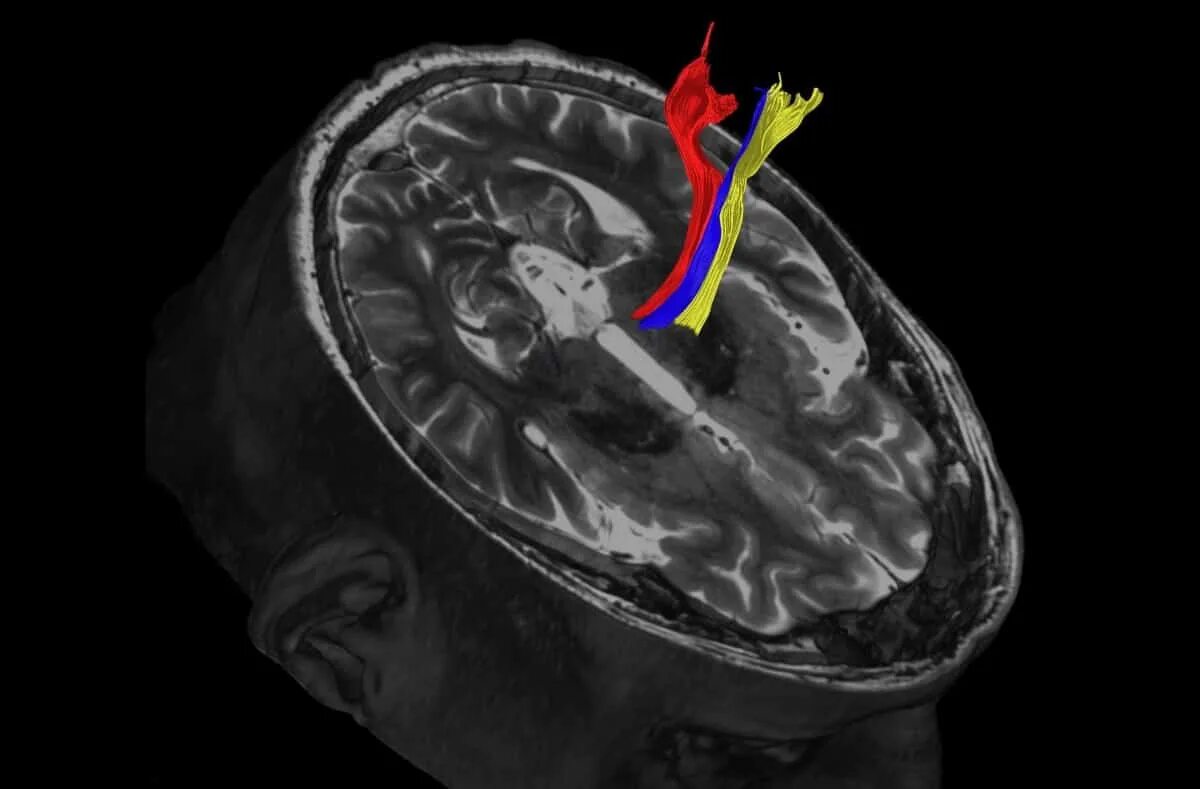

После мрт головного мозга